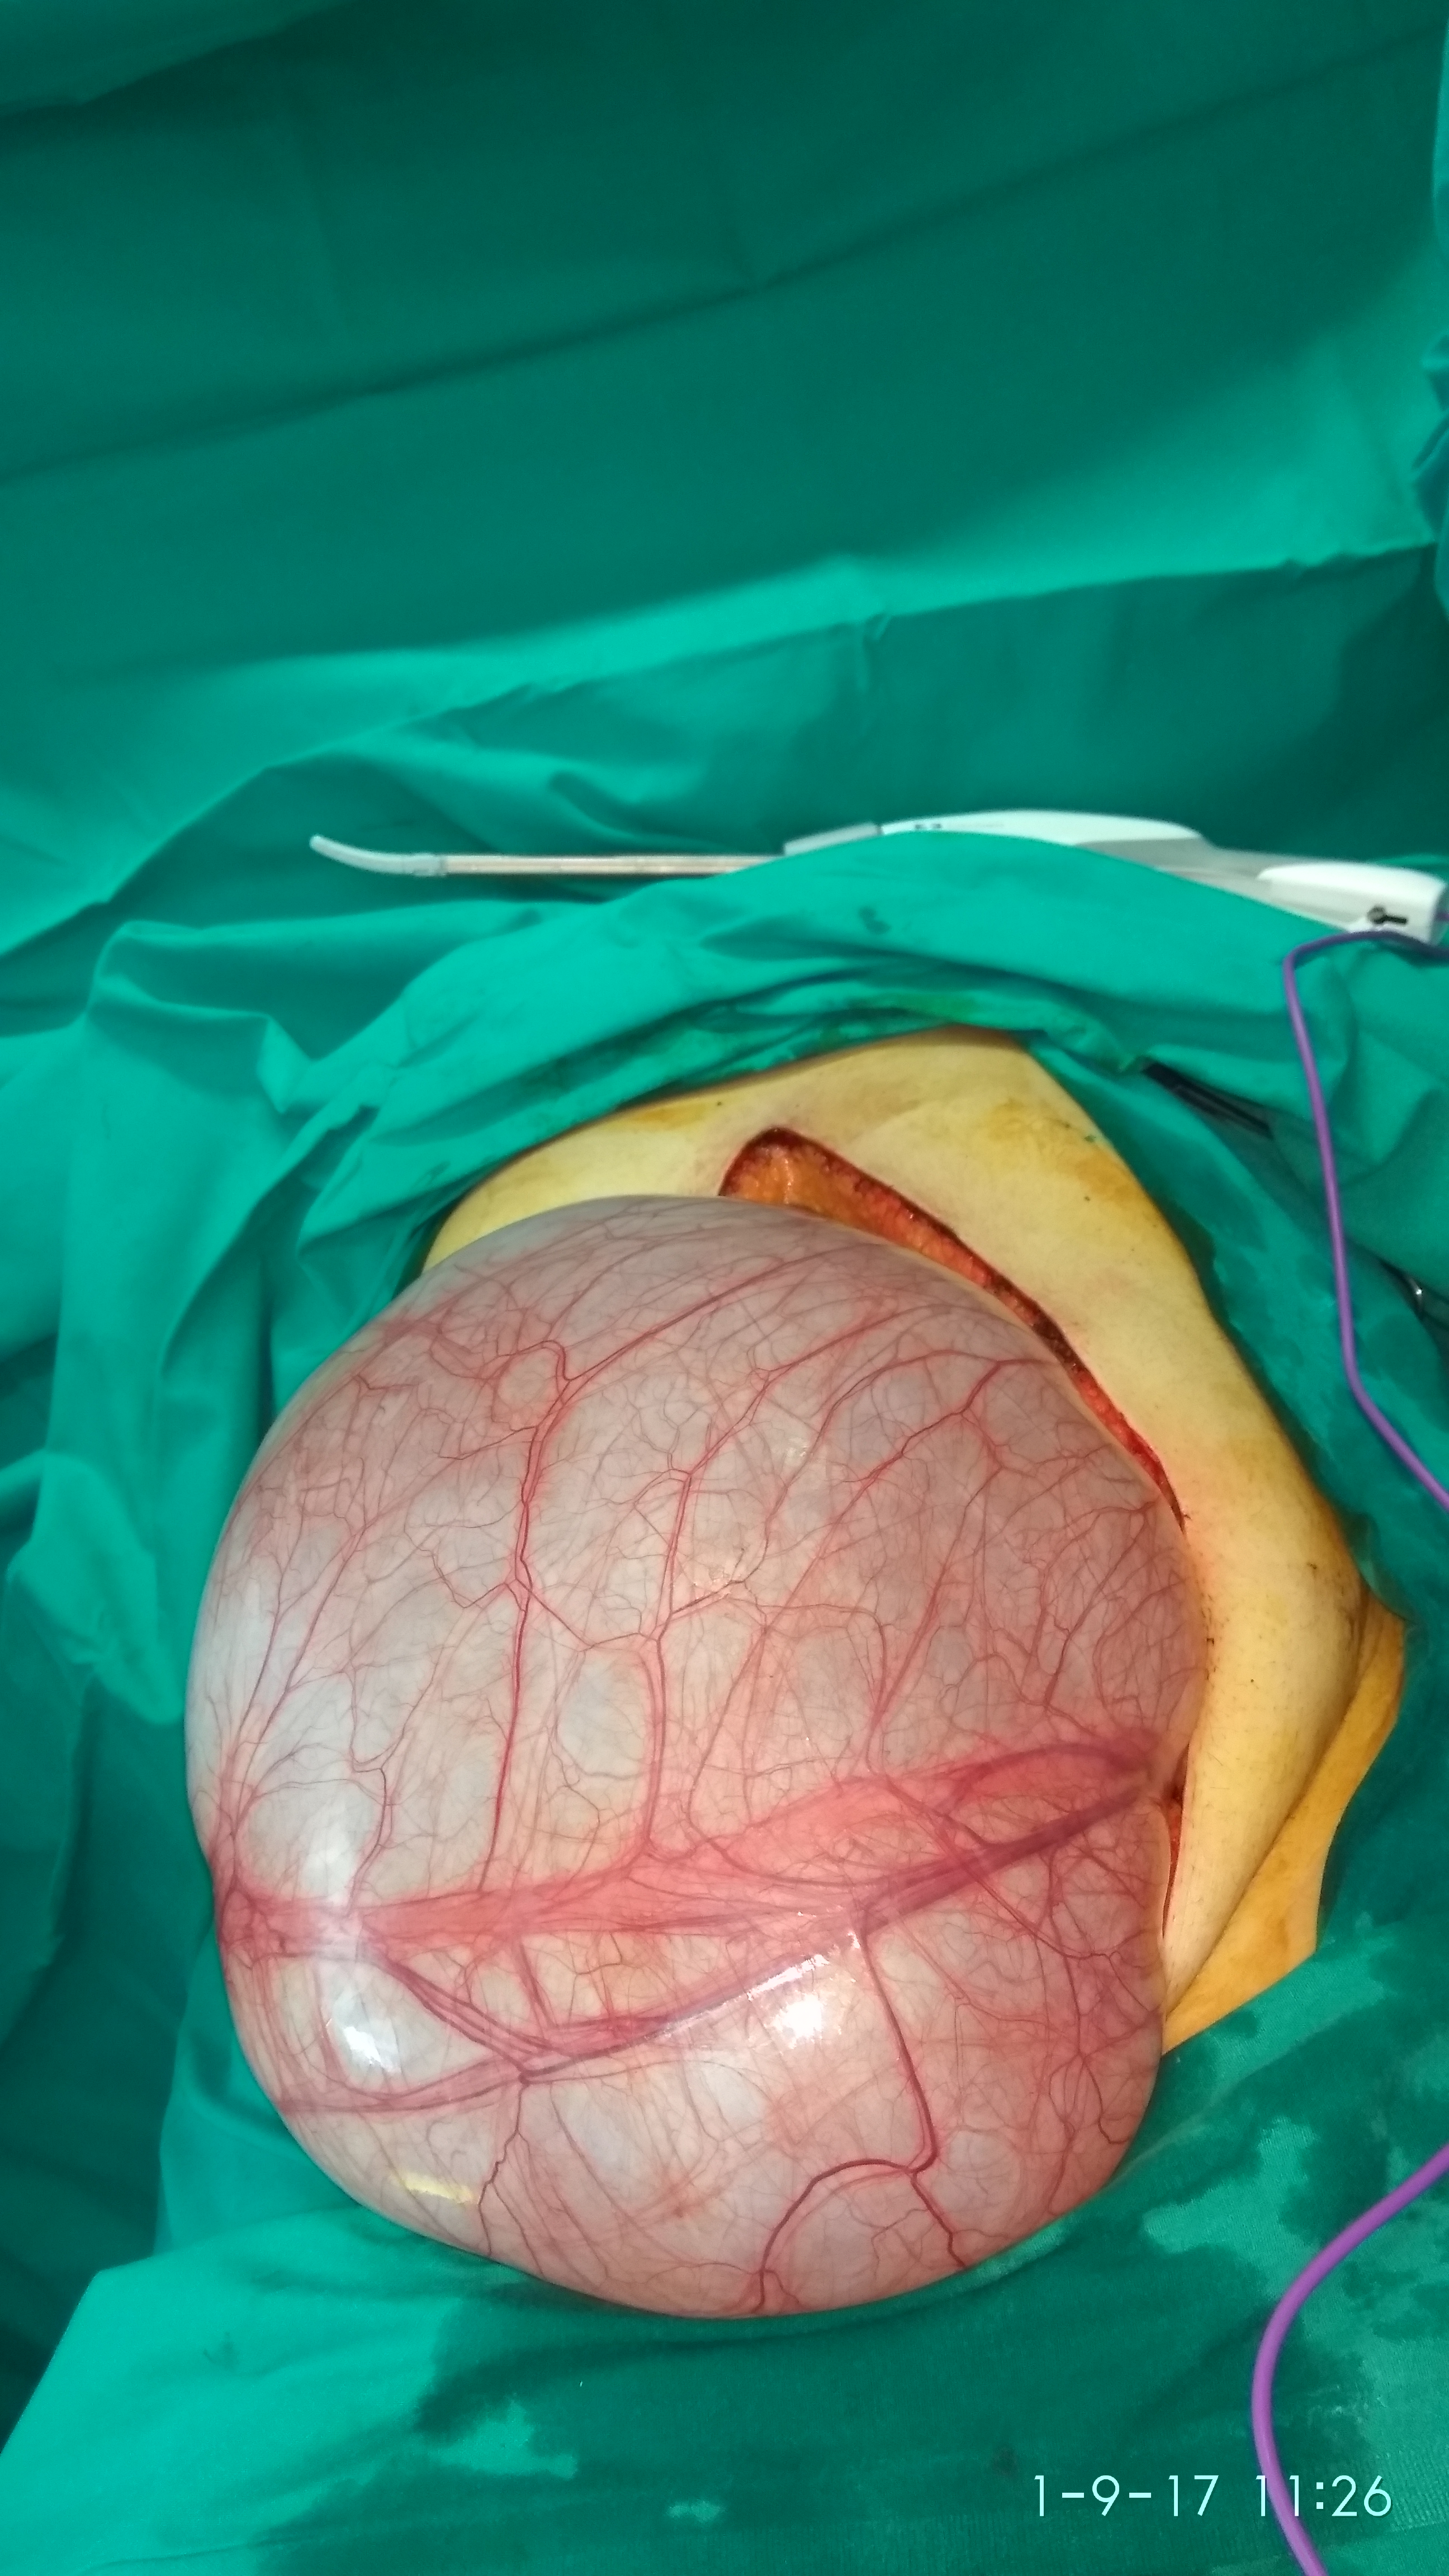

The Huge Ovarian Cystadenomas delivered from the abdominal cavity (Courtesy Dr. V. Penopoulos)